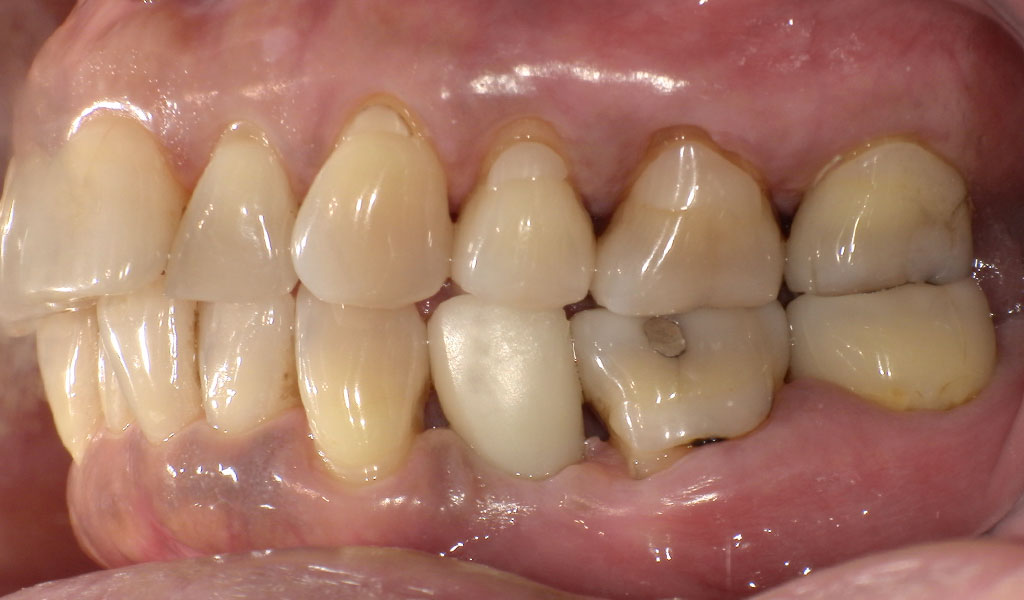

Before3

After3